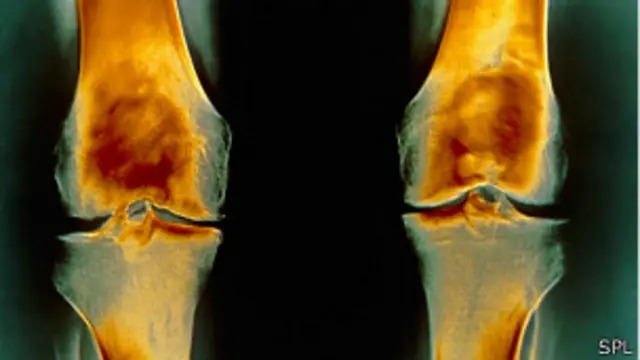

ब्रोकली खाओ, जोड़ों के दर्द से छुटकारा पाओ

ब्रिटेन के शोधकर्ताओं का मानना है कि खूब सारी ब्रोकली खाने से गठिया की बीमारी ठीक हो सकती है. यूनिवर्सिटी ऑफ ईस्ट एंग्लिया के एक दल ने प्रयोगशाला में मिली सफलता के बाद अब इसका इंसानों पर परीक्षण शुरू किया है.

इससे पहले कोशिकाओं और चूहों पर किए गए प्रयोगों से पता चला कि ब्रोकली से हड्डियों को नुकसान पहुंचाने वाले एक प्रमुख विनाशकारी एंजाइम को ब्लॉक करने में मदद मिलती है.